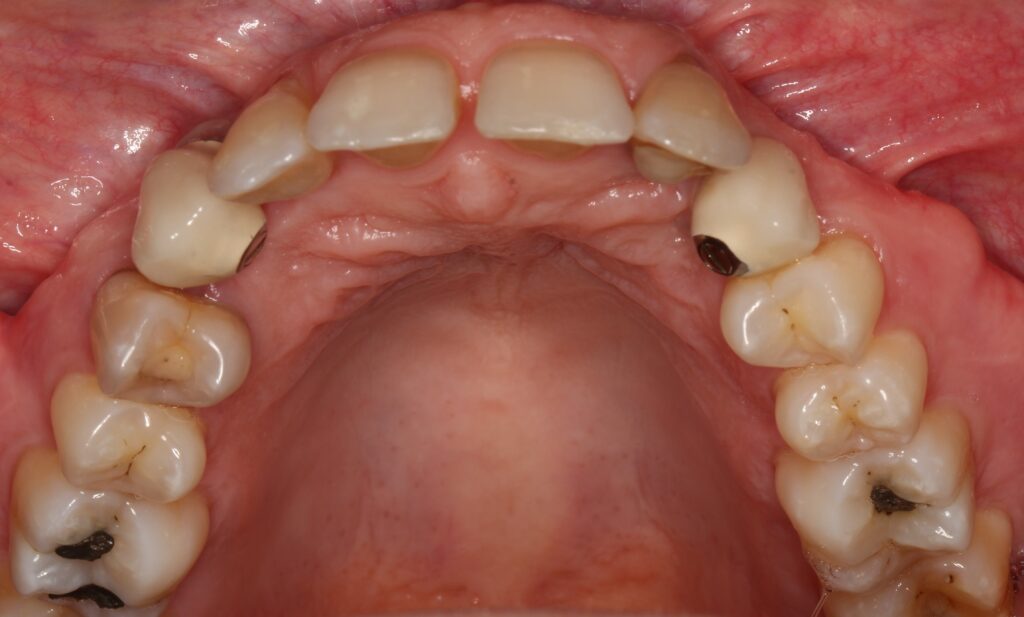

A selection of partial arch fixed implant bridge patients